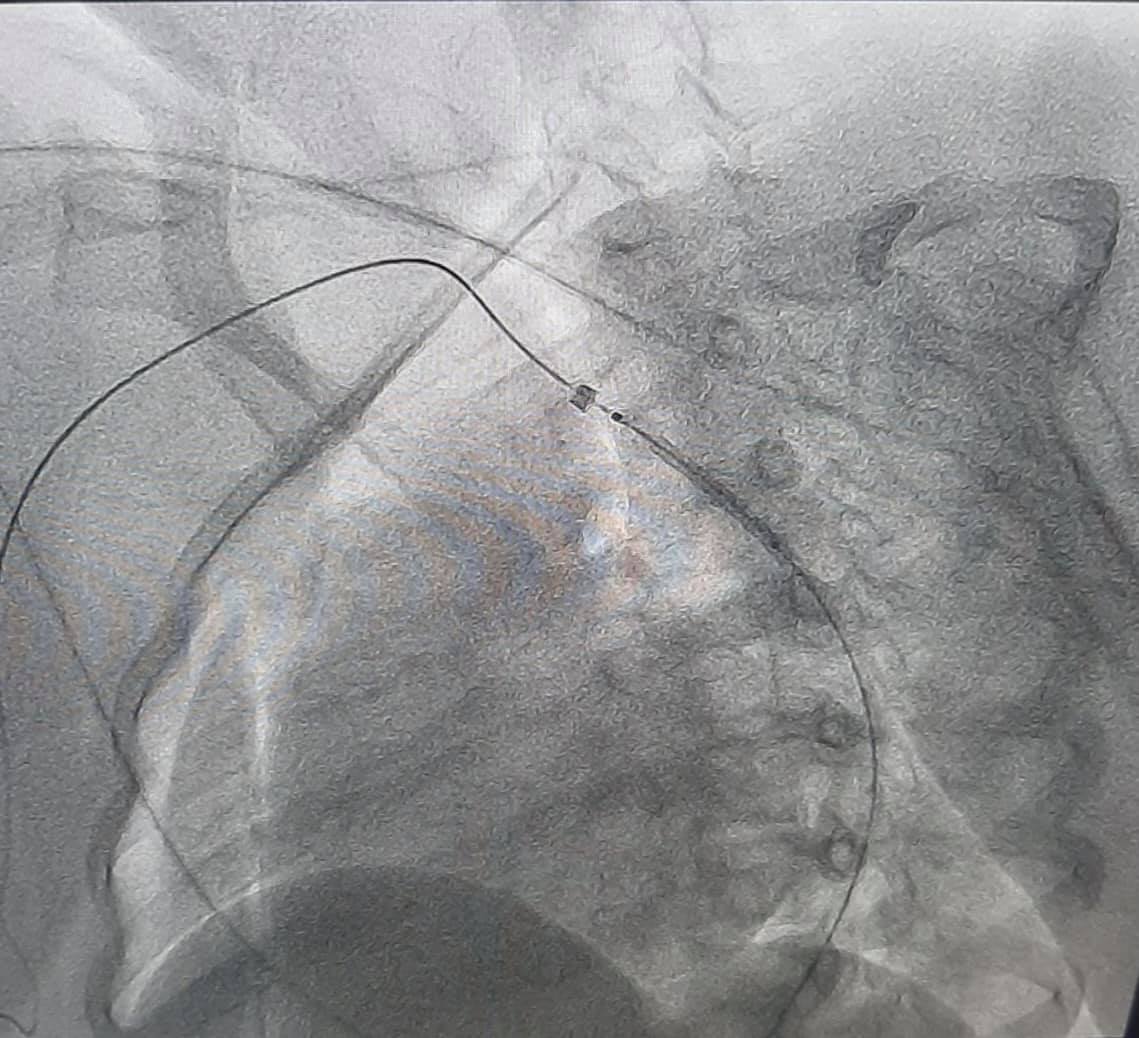

При обстеженні у дівчинки виявили вроджену ваду серця - коарктацію аорти. Це стан, при якому звужений просвіт аорти, внаслідок чого розвивається підвищений тиск у верхній половині тіла.

Сучасні технології на основі результатів обстеження допомогли провести віртуальну реконструкцію анатомії аорти і її гілок. Це допомогло медикам вибрати найбільш сучасну і малотравматичну тактику подальшого лікування.

Вроджена вада судини була ліквідована за допомогою малоінвазивної ендоваскулярної процедури - встановлення стента в просвіт судини.

"Результат лікування не забарився і відразу після оперативного втручання у дитини нормалізувався артеріальний тиск, а також зникла різниця тиску між верхніми і нижніми кінцівками", - повідомили медики.